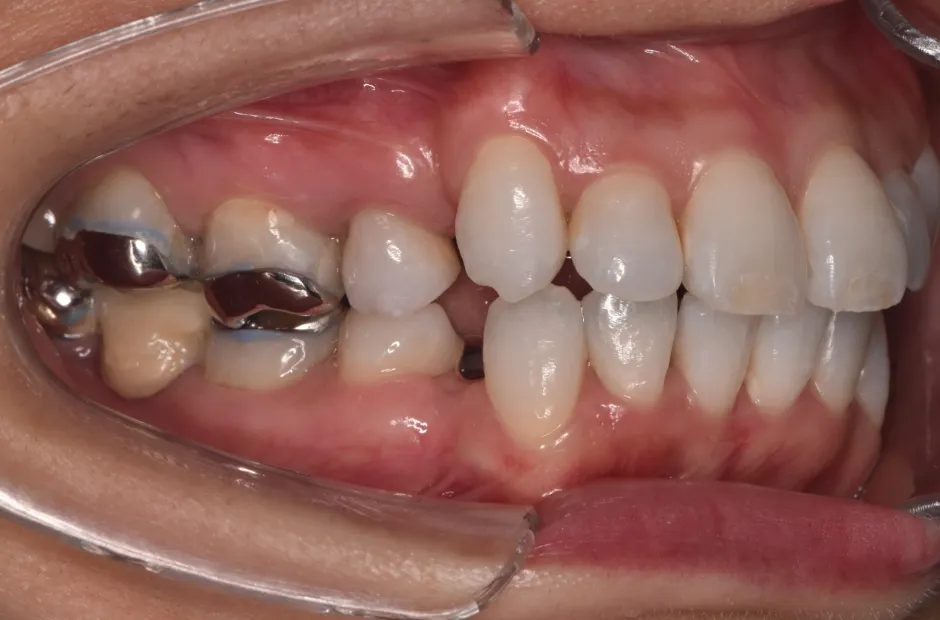

反対咬合

| 診断名・主訴 | 下顎前突、叢生 |

|---|---|

| 年齢・性別 | 23歳・女性 |

| 治療期間・回数 | 3年 |

| 治療に用いた主な装置 | 上顎5,5 下顎4,4 |

| 抜歯部位 | 舌側矯正 |

| 治療費 | 100万円(税抜) |

| リスク・副作用 | 装置による違和感・疼痛・歯肉退縮・歯根吸収・虫歯のリスクなど |

治療前

治療中

治療後